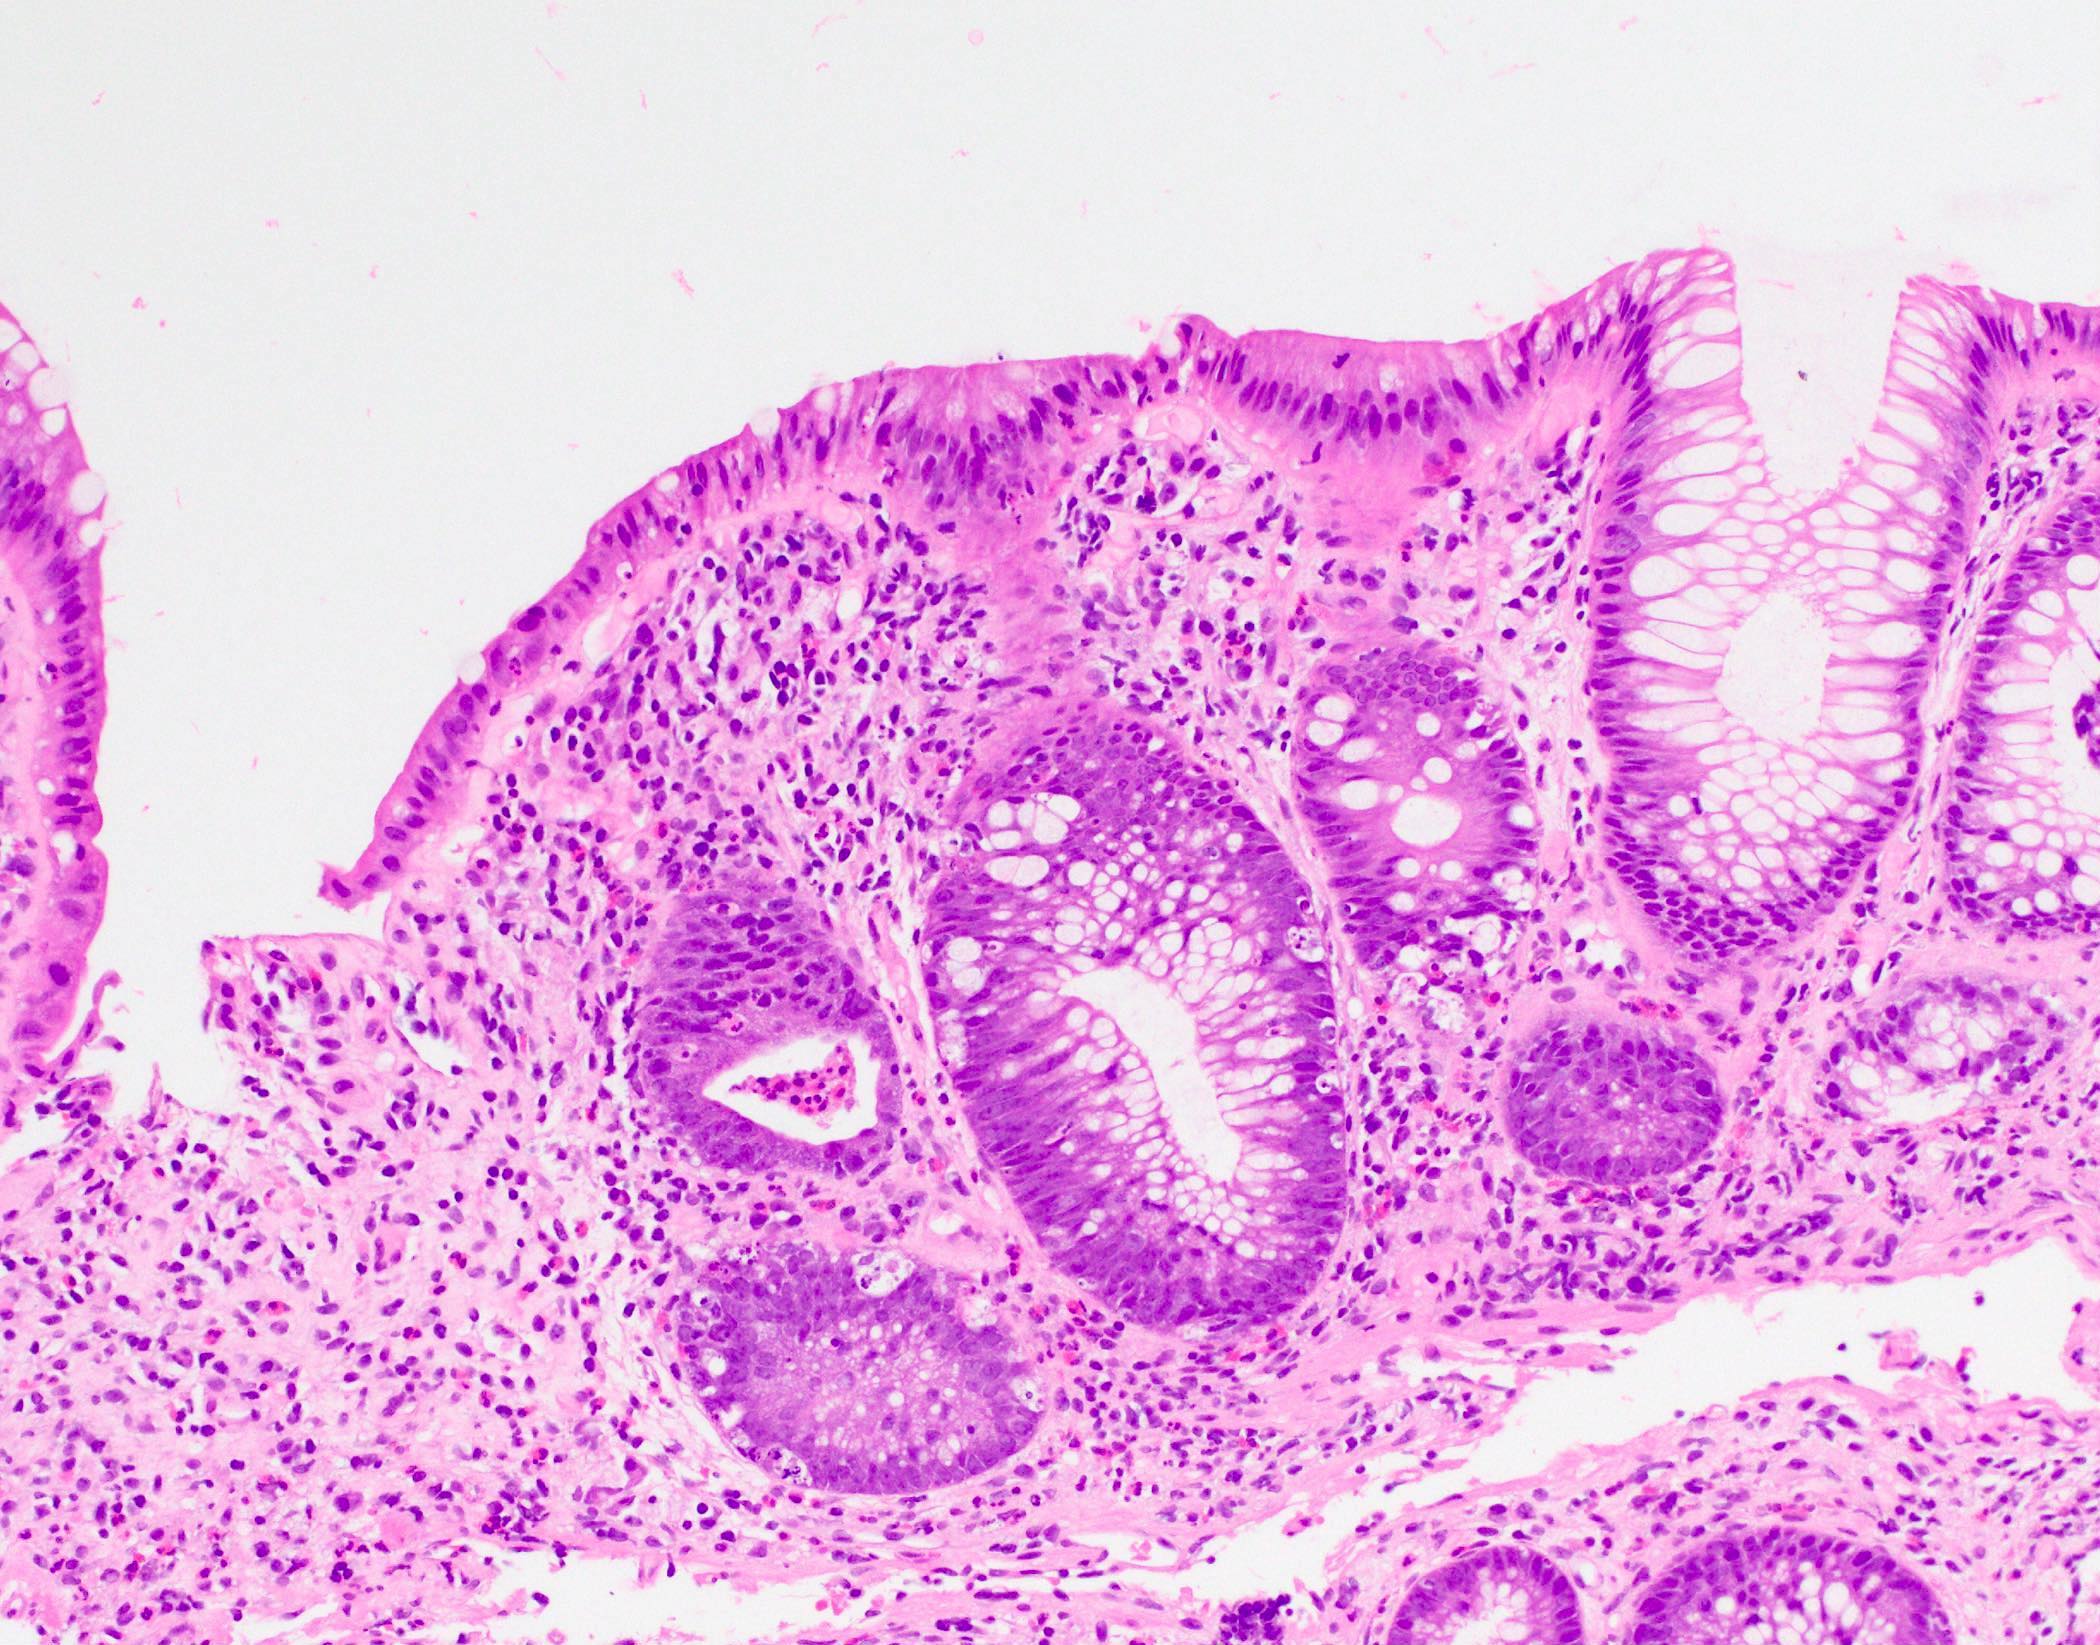

- Characteristic histologic features include crypt apoptosis, crypt dropout and ulceration (Biol Blood Marrow Transplant 2015;21:589)

- Inflammation is generally sparse

- Endocrine cell nests may be seen (Am J Surg Pathol 2013;37:1319)

- Fibrosis and crypt architectural changes are markers of longstanding disease but not specific features of chronic graft versus host disease (Am J Clin Pathol 2016;145:591)

- Apoptosis in the colon is not specific to graft versus host disease and the lower diagnostic threshold is debated

- National Institute of Health proposes ≥ 1 apoptotic body per biopsy fragment (Biol Blood Marrow Transplant 2015;21:589)

- Others propose > 6 apoptotic bodies per 10 contiguous crypts for definitive diagnosis of graft versus host disease (Am J Surg Pathol 2013;37:539)

- Cases with ≤ 6 apoptotic bodies per 10 contiguous crypts are considered indeterminate for graft versus host disease (Histopathology 2016;69:802)

- Utility of histologic grading is questionable because of poor correlation with patient outcome

- When grading is performed, the Lerner system is most commonly utilized

- Grade I: crypt apoptosis without crypt dropout

- Grade II: single crypt dropout

- Grade III: contiguous crypt dropout

- Grade IV: diffuse crypt dropout with ulceration

- When grading is performed, the Lerner system is most commonly utilized

- Graft versus host disease in autologous stem cell transplant patients shows more prominent crypt apoptosis but is otherwise histologically identical to allogeneic graft versus host disease (Mod Pathol 2018;31:1619)

- Histologic examination of at least 8 serial sections is recommended to avoid missing rare apoptotic bodies (Biol Blood Marrow Transplant 2015;21:589)

Microscopic (histologic) images